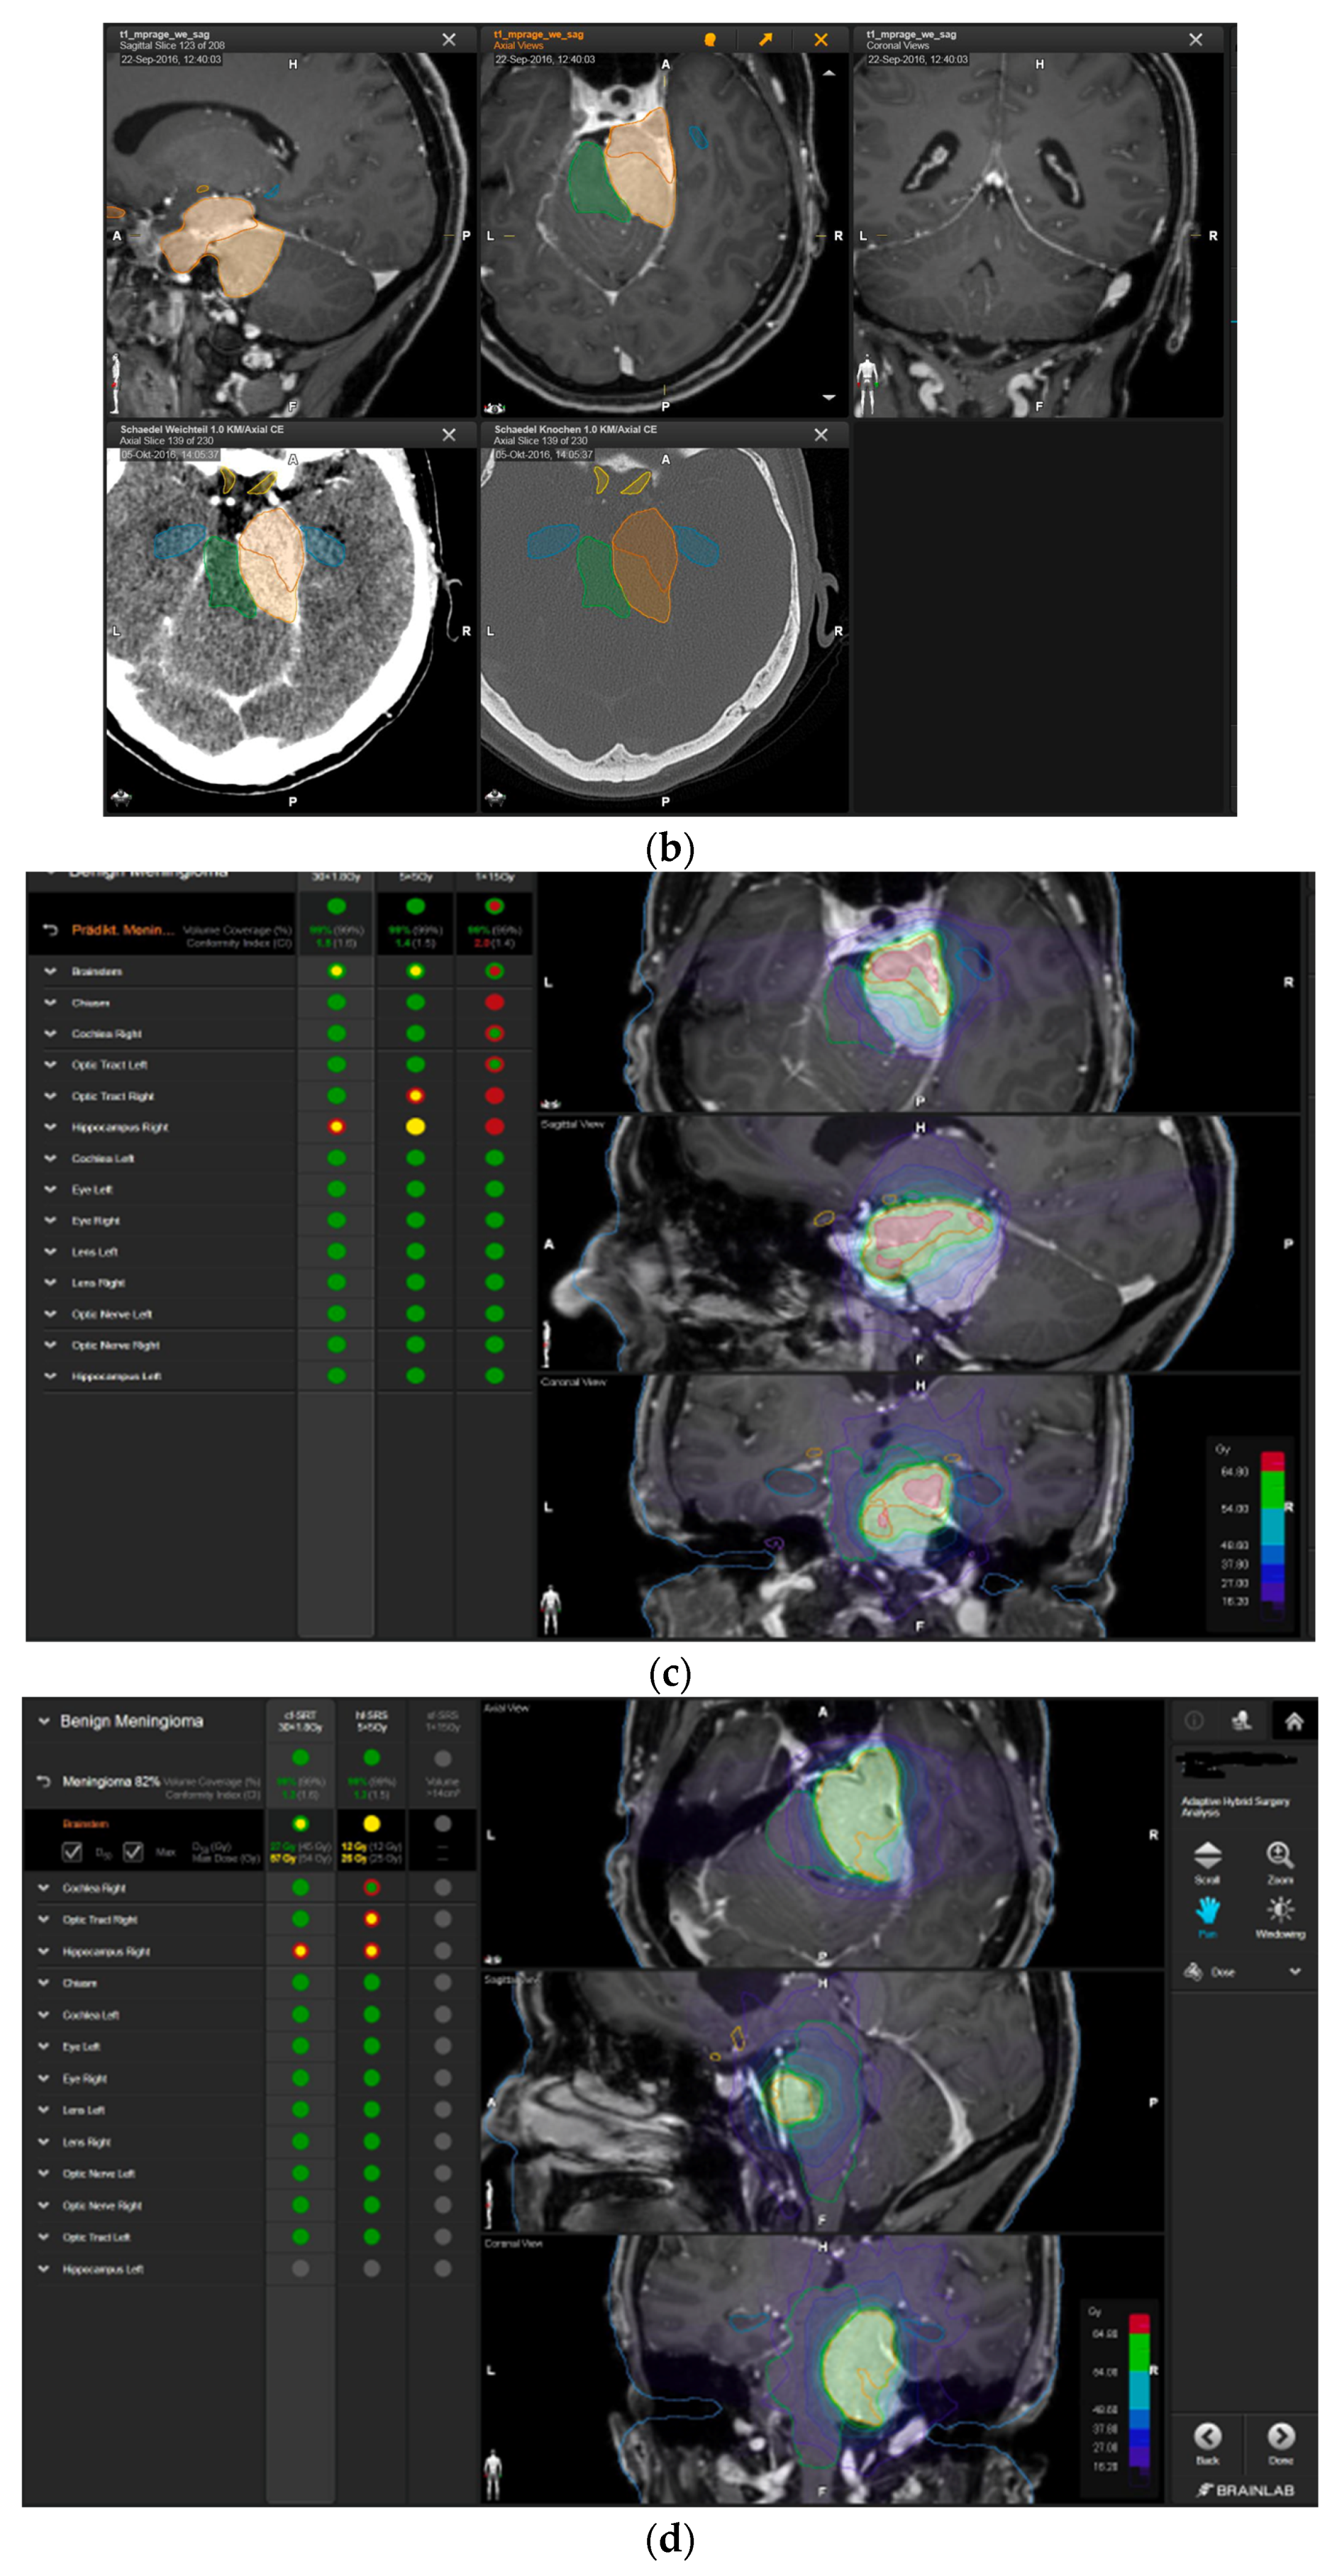

A 50-year-old woman presented with aggravated headache, neck pain, and burnout symptoms. Detailed neuropsychological testing confirmed a frontal behavioral syndrome (Figure 3). The patient underwent elective craniotomy and tumor resection with AHSA technology. After complete recovery from the surgery, hypofractionated radiosurgery was performed (5 × 5 Gy) to treat the remnant tumor 1.5 years after resection.

Figure 3.

First representative case with AHSA-assisted tumor resection. (a) Preoperative MRI imaging of tumor (orange) and planned residual tumor volume (red). (b) Dose constraints in the AHSA software for conventional, hypofractionated radiotherapy, and radiosurgery planning for the preoperatively defined residual tumor volume. With this plan, conventional fractionated and hypofractionated radiotherapy were feasible, with effective tumor coverage.

—brainstem: max. dose is marginally safe, whereas mean dose is safe. For single fraction stereotactic radiosurgery, the tumor volume coverage seems effective, while the conformity index was indicating over-treatment.

—brainstem: mean dose is safe, while max. dose is unsafe;

—chiasm: mean dose is unsafe, while max. dose is safe;

—right optic tract: mean dose is unsafe, while max. dose is safe. (c) First intraoperative structure update (ISU) at the time point of 65% residual tumor volume, showing the tumor coverage and organ at risk constraints. At this stage of the resection, AHSA demonstrated that only conventional and hypofractionated radiotherapy were feasible.

—brainstem: max. dose is marginally safe, whereas mean dose is safe. (d) Second ISU acquisition and residual tumor reduction to 58%. (e) Third ISU acquisition with a reduction of residual tumor volume to 41%. Dose constraints for conventional, hypofractionated radiotherapy, and radiosurgery are demonstrated. At the final stage of the resection, the conventional and hypofractionated radiotherapy organ risk constraints were unchanged.

—brainstem shows that max. dose is marginally safe, whereas mean dose is safe. The single-dose stereotactic radiosurgery constraints show that:

—brainstem: mean dose safe, max. dose unsafe;

—chiasm: mean dose unsafe, max. dose safe;

—right optic tract: mean dose marginally safe, max. dose unsafe. (f) Fusion of intraoperative CT to final intraoperative ISU. (g) Preoperative and 3 months postoperative MRI imaging for planning of radiosurgery (5 × 5 Gy).